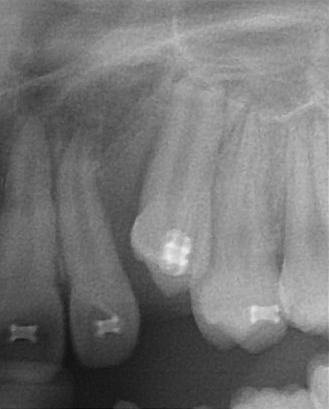

患者陳小妹妹(治療時僅9歲),於本院接受齒顎矯正治療,經數位X光(圖二)診斷,左側乳犬齒之上尚有埋伏的恆牙犬齒為假牙,使用口內攝影(圖二)與病患解釋,建議患者處理方式如下:

圖二 |